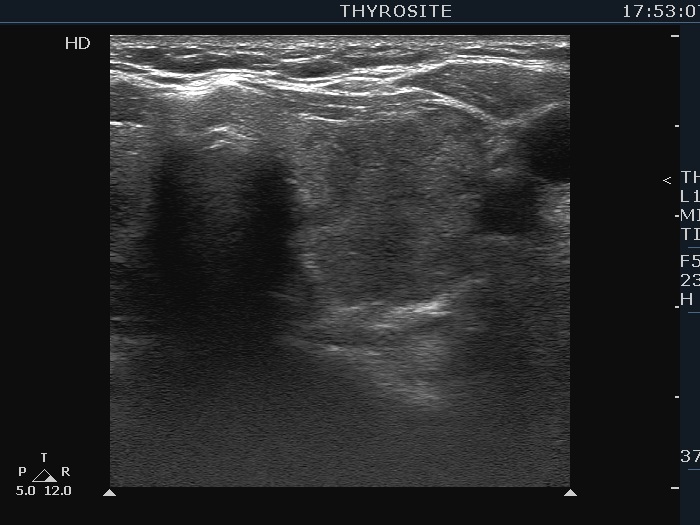

Three years after the first examination (third row of images):

Clinical presentation. The patient has ceased the thyrostatic therapy for six months. Recently, she noticed again complaints suggesting hyperthyroidism.

Palpation: unchanged.

Results of blood tests: hyperthyroidism (TSH undetectable, FT4 39.1 pM/L).

Ultrasonography. There were two changes compared with the previous examination. The thyroid has become echonormal while the lesion in the right lobe has become again hypoechoic.Suggestion: daily 20 mg methimazole. Radioiodine therapy when the FT4 level will become normal.

- This case demonstrates the exception and not the rule. The echogenicity of a nodule almost always remains the same even over decades while in this patient the echogenicity has significantly changed two times within three years. The possible explanation is that the basic echo pattern of the extranodular thyroid and the vascularization influenced the pattern of the lesion.

- It is not evident whether the lesion in the right lobe is a single nodule with lobulated margins or a mass composed of multiple discrete lesions. In the former case the lobulation is pathological in the latter the undulation is not.